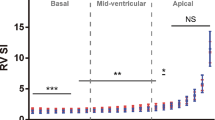

Strain analysis

First, a mean ± SD was calculated for patients with normal hearts to establish a baseline for our lab. This was − 22.6% (95% CI -24, -21.1) for LV and − 22.1% (95% CI -23.6, -20.6) for RV. Thereafter, mean ± SD were calculated for the AVC and dTGA groups, and the three groups (Normal, dTGA and AVC) were compared. A significant difference was noticed in the mean GLS between the AVC group and the other two groups with fetuses in the AVC group having a significantly higher strain compared to both dTGA and normal patient for both LV and RV measurements (Table 2) (LV p = 0.003, 0.0001, RV p = 0.0001, < 0.0001). However, there was no statistically significant difference between the dTGA and normal group (Table 2) (LV p = 0.96, RV p = 0.8). The differences remained the same after adjusting for gestational age.

GCS

In contrast to GLS, the GCS in the AVC and dTGA patients was significantly higher than the normal group. The average strain in the AVC group was higher by 4.3% (95% CI: 7.9, 0.5; p = 0.021) compared to normal group while the average strain was higher by 5.2% (95% CI: 9.7, 0.6; p = 0.022) in the dTGA group compared to normal. No significant difference was seen between the AVC and dTGA (p = 0.87) groups, however (Table 4). Similar results were observed adjusting for effect of gestational age.

Finally, the intra-rater and inter-rater reliability were assessed and showed a good intra-rater agreement with an intraclass correlation coefficient of 0.94 (CI of 0.80, 0.99) for RV GLS, 0.98 (CI of 0.92, 0.99) for LV GLS, and 0.99 (CI of 0.98, 0.99) for LV GCS (Fig. 3).

However, the inter-rater agreement was fair to poor with an intraclass correlation coefficient of 0.31 (CI of 0.00, 0.89) for RV GLS, 0.74 (CI of 0.12, 0.92) for LV GLS, and 0.27 (CI of 0.00, 0.72) for LV GCS (Fig. 4).